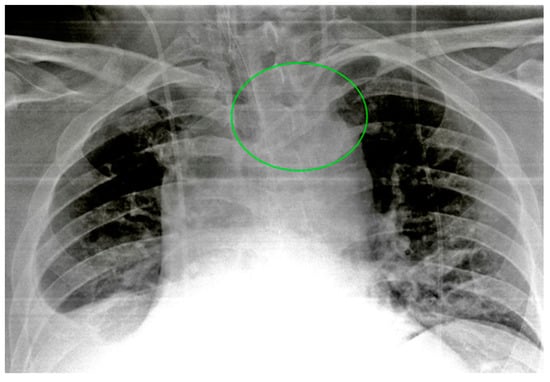

6.1. Nasogastric Tubes

6.2. Nasoenteric Tubes